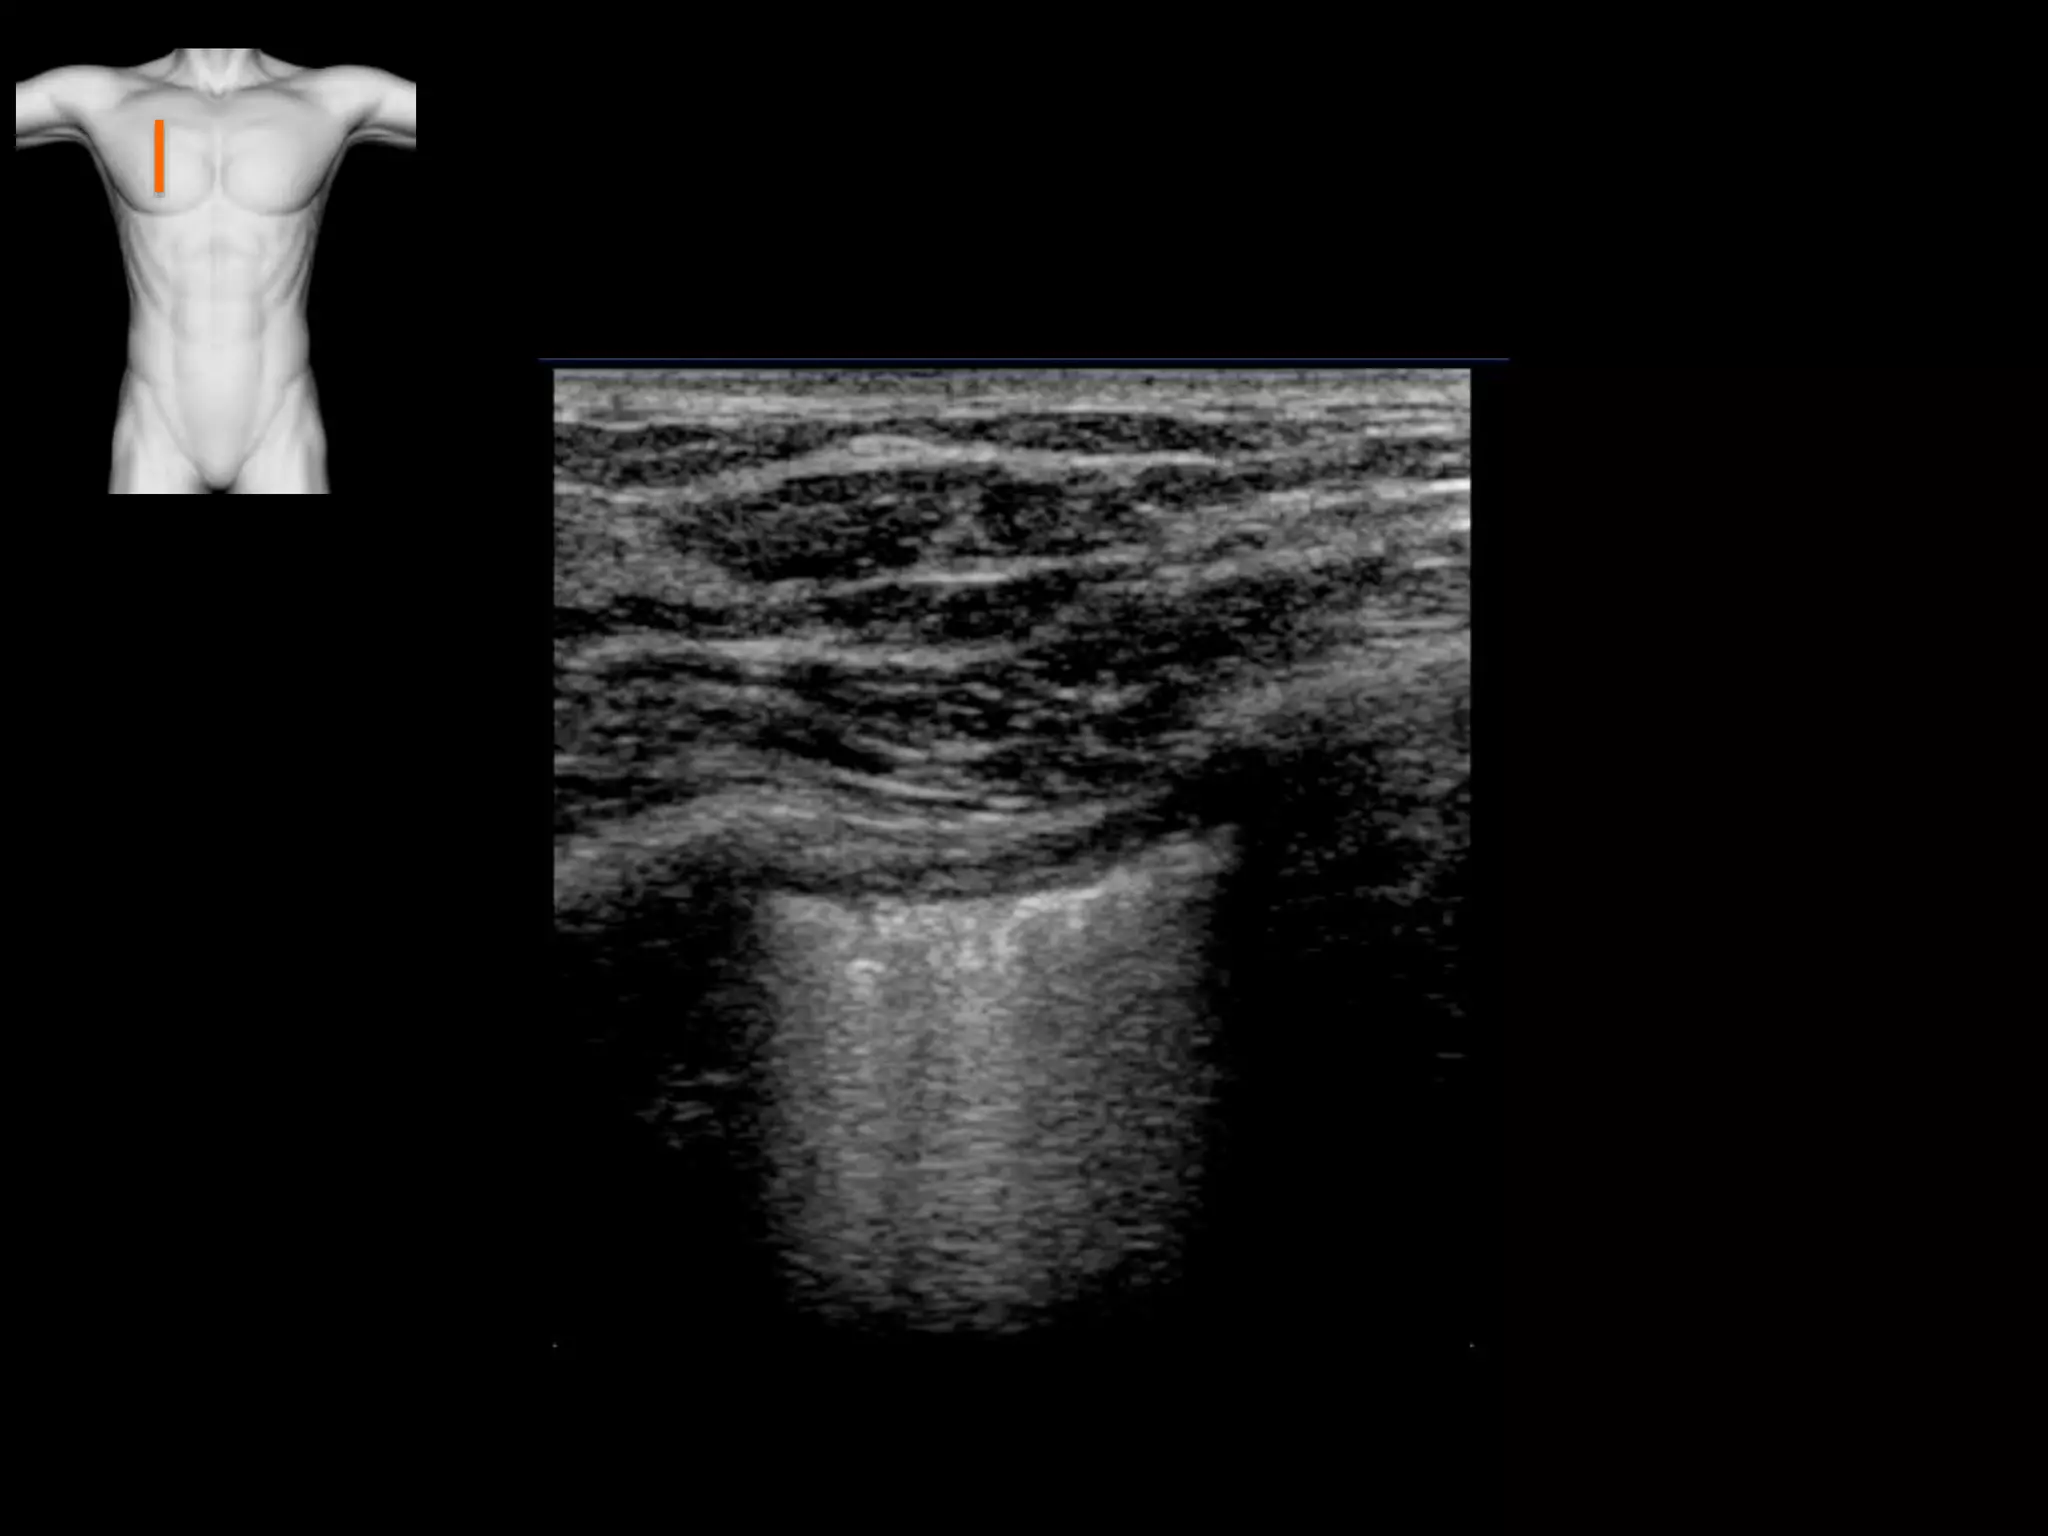

Consolidation

Solid lungs: Hepatisation, air bronchograms,

Atelectasis (compression / resorption), haemorrhage, tumour, infarction

• Consolidation

• Hepatisation, air bronchograms, shred sign